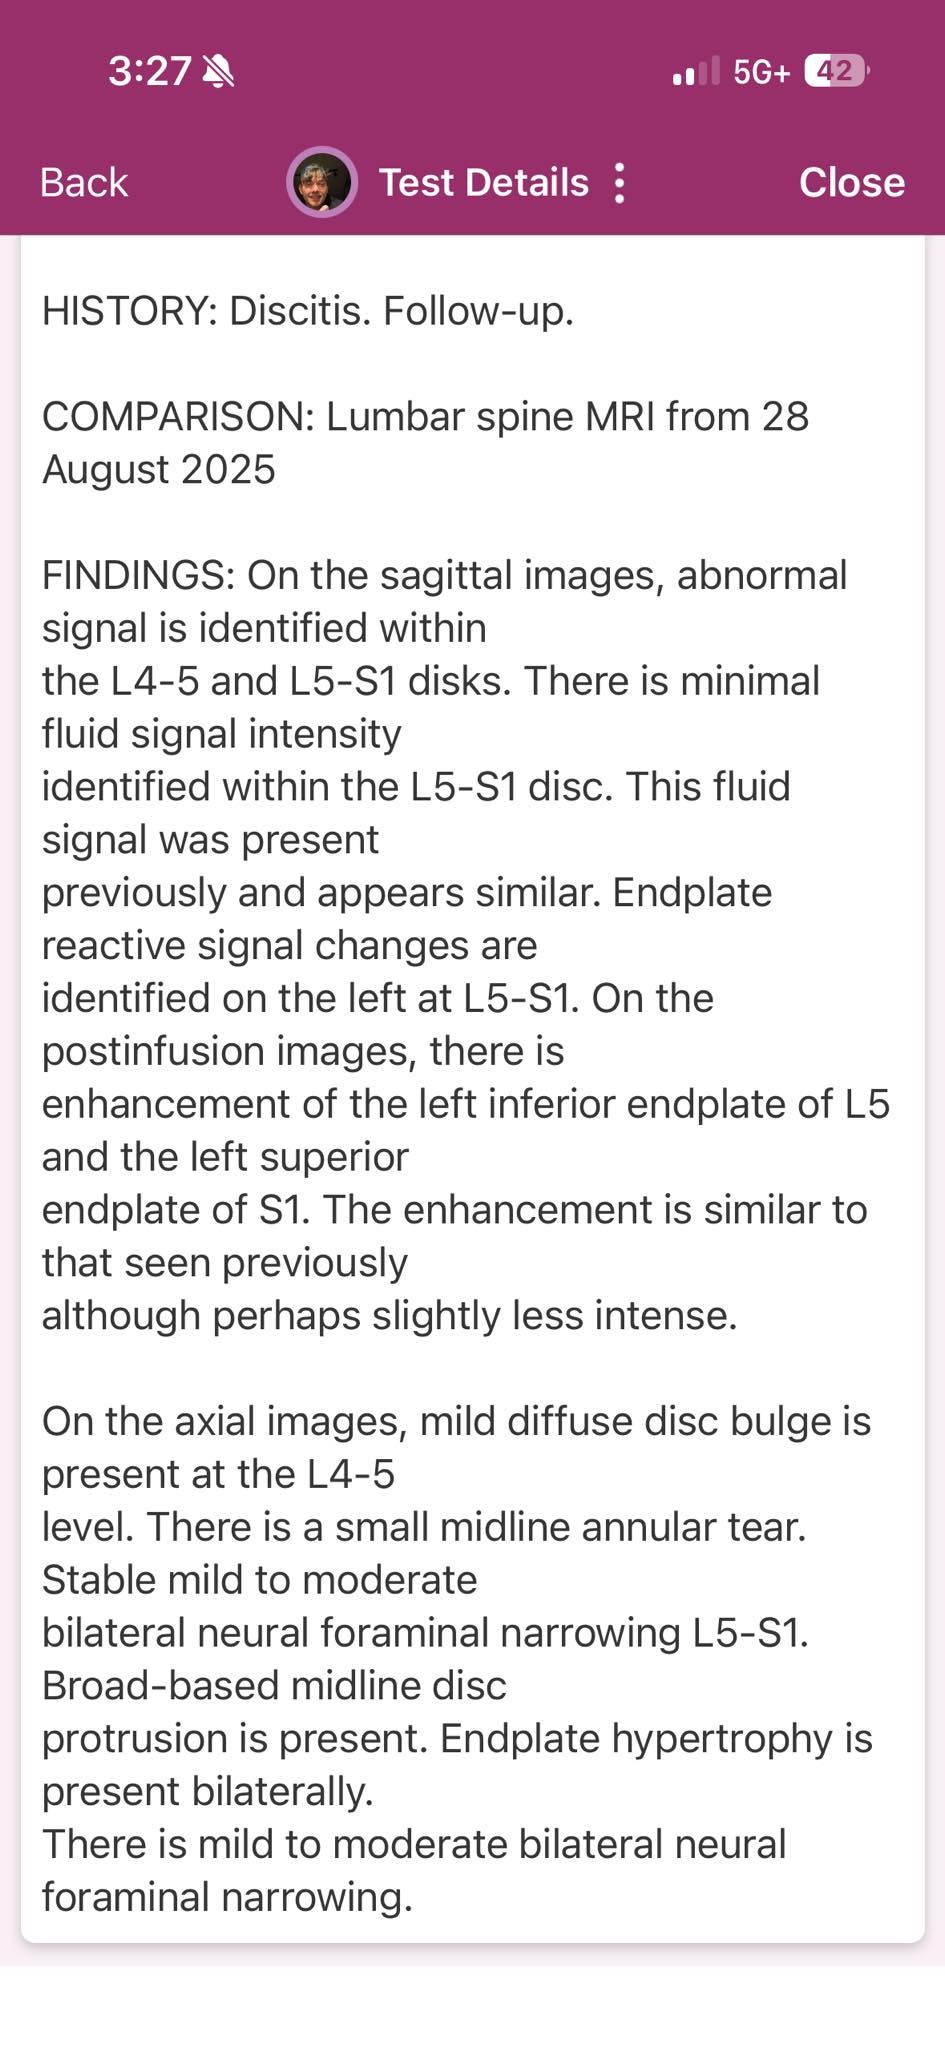

-Derek currently has two potentially deadly infections in his spinal cord, along with IDH Mutant or Astrocytoma, which is a brain cancer that there is currently no cure for. On top of all of this, he has developed 3 masses on and in his liver. With his current regimen of over 20 pills a day, driving to Lexington for appointments 6-8x a week and to Vanderbilt often, as well being a Dad and continuing his duties there, the financial burden has been significant. He has been fighting disability which feels like a losing battle for 2 years. -

Derek has been facing an ongoing battle with brain cancer and other medical issues. Most recently, he learned that he has a severe infection on his spinal cord, a cancerous tumor in his brain, as well as his liver. He has had to have a PICC line put in, and will be down for at least 8-10 weeks, if not longer. Insurance is being a pain and not wanting to cover many parts of his treatment, including home health, which is causing him to have to stay in the hospital, and miss valuable time with his son and best friend, Jayden.

Unfortunately, nothing can be done as far as treatment for cancer until the infection is gone. He could really use some help right now to ease the financial burden and focus on healing through his treatments. If you feel led to donate, 100% of the proceeds will go directly to him. Thanks in advance!